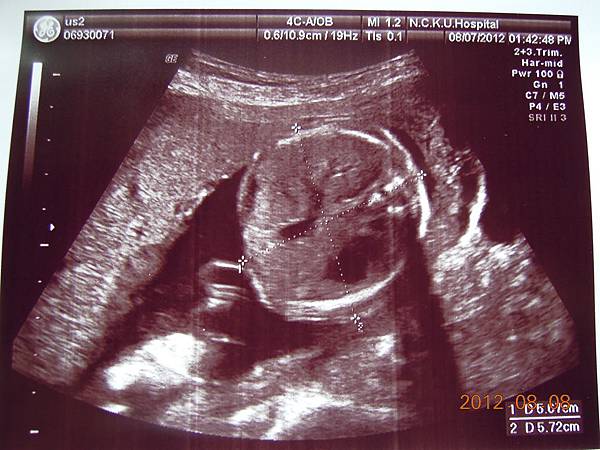

可以看到的是在逼逼的上方剛好被胎盤擋著,比較看不到他的正面,除了肛門無法看到(怕沒有肛門),醫師說現在看不到,小雞雞也沒照他的大小(我怕他發育不良),其他身體器官包括腦部剖有量測他的大小及羊水多寡(我怕像上次一樣羊水太少),今天量出來是12,喔彌陀佛~~

大約檢查了有四五十分鐘,也數了他的手指腳趾,看起來是沒異狀,就叫我等下把報告拿過去門診給游醫師看,還給我ㄧ堆照片,就是下面那些~~

這是他給我的報告,都是一些代號,游醫師說明很快,不過我聽他說沒問題,就比較放心,裡面有把每個器官大約生長到幾週做個說明,大致都在22~24周,逼逼體重約697g~

高層次超音波報告~~

接下來就是他的一堆檢查照片啦~~